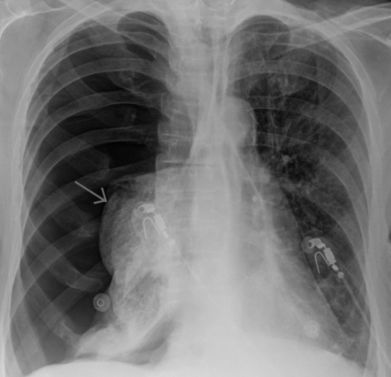

Пневмония и плеврит

Заболевания органов дыхания нередко сопровождаются болью справа. Это наблюдается при нижнедолевой пневмонии или плеврите. Подобный признак локализуется не только спереди, но и сзади – на стороне патологии. Болевые ощущения, как правило, связаны с дыханием, а при плеврите уменьшаются в положении лежа на пораженном боку. При двустороннем процессе они нередко имеют опоясывающий характер. Также присутствуют и другие жалобы:

- Кашель.

- Выделение мокроты.

- Одышка.

- Лихорадка.

Мокрота будет выделяться при пневмонии, а плеврит не сопровождается таким признаком. Диагноз можно поставить даже клинически – благодаря перкуссии и аускультации.

Патология органов дыхания часто сопровождается болью под ребрами, что нужно учитывать при дифференциальной диагностике.